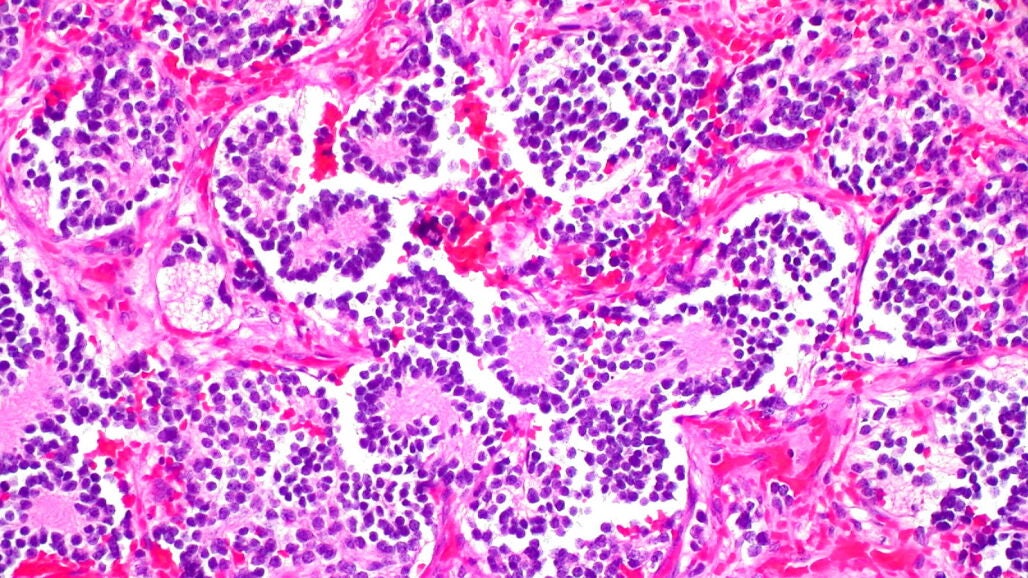

La terapia de diferenciación es un método de tratamiento utilizado en el neuroblastoma que busca transformar las células cancerosas en células más maduras y sanas. El problema con la terapia de diferenciación actual con ácido retinoico es que muchos pacientes no responden al tratamiento y aproximadamente la mitad desarrollan resistencia, lo que pone obstáculos y deriva en efectos secundarios en pacientes que no tienen muchos recursos inmunológicos para pelear.

El siguiente paso del equipo de Arsenian Henriksson, es evaluar los efectos del tratamiento en un ensayo clínico para investigar su seguridad y eficacia en niños. Uno de los inhibidores ya ha recibido la designación de medicamento huérfano (aquellos que no se desarrollan por motivos económicos) de la Administración de Alimentos y Medicamentos de Estados Unidos para el tratamiento de un diagnóstico diferente en adultos, lo que lo convierte en un candidato a fármaco particularmente prometedor.